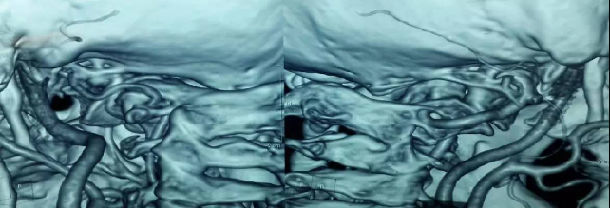

3影像学检查

手术前前屈位X光片寰枢椎脱位(寰齿前间隙7mm)。寰枢椎三维CT见寰枕融合,颅底陷入(齿状突位于钱氏线上14.2mm),右侧枢椎椎弓根发育狭小(小于2mm),磁共振显示小脑扁桃体下疝、颈髓损伤伴椎管狭窄。

全麻后,显微镜下行颈后路减压+枕颈撑开复位椎弓根侧块(左侧枕骨-C2~3,右侧枕骨-C3)螺钉钛棒内固定+植骨融合术。术中C臂下行枕颈撑开复位椎弓根侧块置钉。术后复查见椎管减压后脊髓位置良好,小脑扁桃体下疝改善,寰枢椎脱位复位。患者症状逐渐好转。